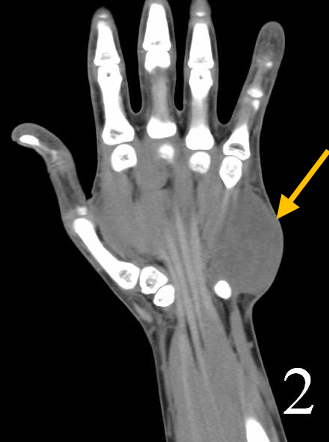

• • The work-up often consists of a physical examination, X-rays, CT scans, MRI, and sometimes bone scans are required. CT scans can be used to check for subtle mineralization that may help with the diagnosis

• • CT of the chest is necessary to check for pulmonary metastases. The lungs and other bones are the to most common sites for the tumor to spread.

Radiographic imaging is used to help form a diagnosis. These include X-Ray, MRI, CT and Bone Scans